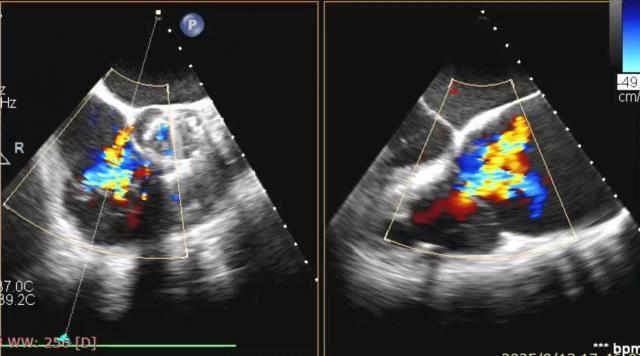

術(shù)前食道超聲顯示三尖瓣重度反流。